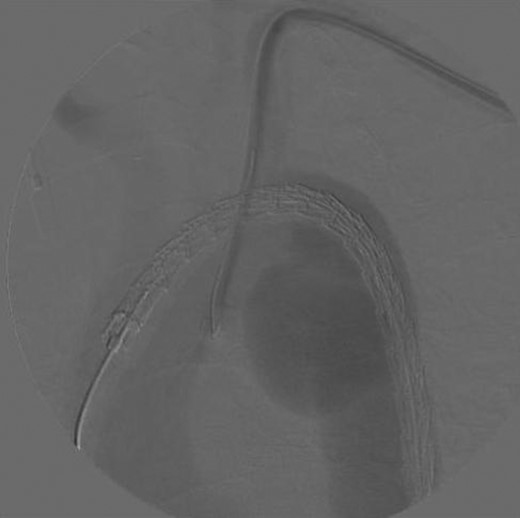

A 74-year-old woman was referred to our vascular service with a 6-month history of hoarseness of voice and intermittent dry cough. The patient’s medical history included hypertension and gastroesophageal reflux disease. Flexible laryngoscopy demonstrated a foreshortened, lateralised and flaccid vocal fold consistent with unilateral vocal cord paralysis. Subsequent computed tomography (CT) imaging of the neck and thorax revealed a saccular aneurysm in the aortopulmonary window measuring 39 mm (Fig. 1). Digital subtraction angiography confirmed the presence of a ductal aneurysm with a well-defined neck and no intraluminal thrombus (Fig. 2). There was no contrast extravasation into the mediastinum or pulmonary circulation. Following a cardiovascular multidisciplinary meeting, treatment options were discussed with the patient and consensus favoured endovascular repair. The distance from the proximal margin of the aneurysmal neck to the origin of the left subclavian artery measured just under 2 cm and therefore did not meet the manufacturer’s minimal landing zone requirements. To circumnavigate this dilemma, a left subclavian stent graft was inserted with its proximal end parallel to the main thoracic endoprosthesis. The procedure was uncomplicated and repeat imaging revealed widely patent stent grafts with satisfactory positioning and absence of endoleak (Fig. 3). Our patient was discharged home on the second postoperative day. She continued speech and language therapy postoperatively and has made remarkable recovery of phonation, declining any further treatment options for same.

Sagittal CT with 3D reconstruction demonstrated a 39-mm saccular aneurysm along the lesser curvature of the aortic arch, expanding in the direction of the pulmonary artery.